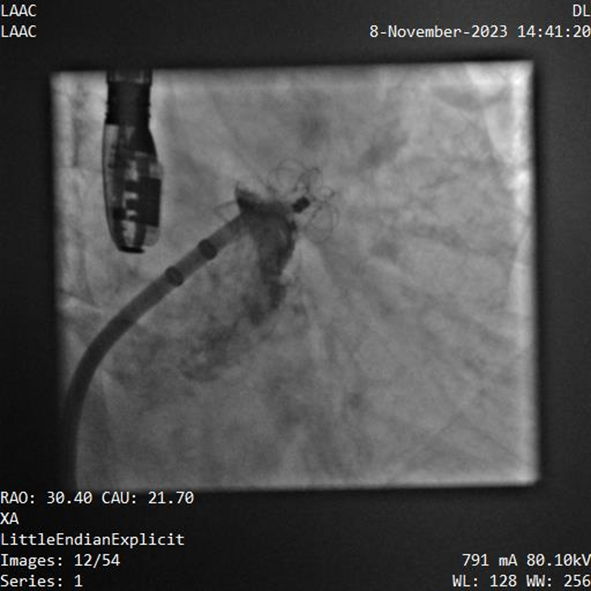

該例患者為男性58歲,陣發(fā)性房顫,9個月前突發(fā)急性腦梗死,3月前曾行房顫射頻消融術(shù)。2023年11月經(jīng)胸超聲心動圖示左房內(nèi)徑46mm,經(jīng)食道超聲心動圖示左心房及左心耳內(nèi)未見血栓形成,CHA2DS2-VASc評分3分,HAS-BLED評分2分。DSA測得左心耳開口直徑約23mm,錨定區(qū)域約18mm。

手術(shù)過程順利,通過植入非常規(guī)固配規(guī)格的固定部20mm、封堵盤28mm的左心耳封堵器,實現(xiàn)左心耳完全封堵,達到手術(shù)預(yù)期效果,再次體現(xiàn)產(chǎn)品獨特的設(shè)計創(chuàng)新優(yōu)勢。

器械釋放后造影示封堵器展開良好,封堵完全